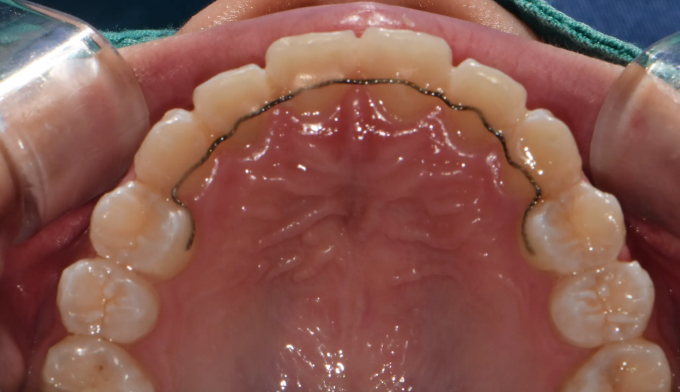

주걱턱, 그리고 앞니가 거꾸로 물리는 ‘반대교합’은 비슷한 말이 아닙니다. 서로 전혀 다른 원인과 치료 방법을 가지고 있습니다.

주걱턱은 턱 자체의 길이가 긴 경우이고, 반대교합은 위아래 앞니 사이의 관계를 지칭하는 말입니다.

턱뼈의 성장이 정상인 경우에는 턱교정 필요없이 앞니만 제대로 넘겨주면 훨씬 간단하고 효율적인 교정치료가 가능합니다.

본 케이스의 홙자는 턱뼈의 모든 수치가 정상이었으므로 치아만 적절히 교정하여 안모의 개선까지 만들어낸 경우입니다. 교정기간은 11개월 소요되었습니다.